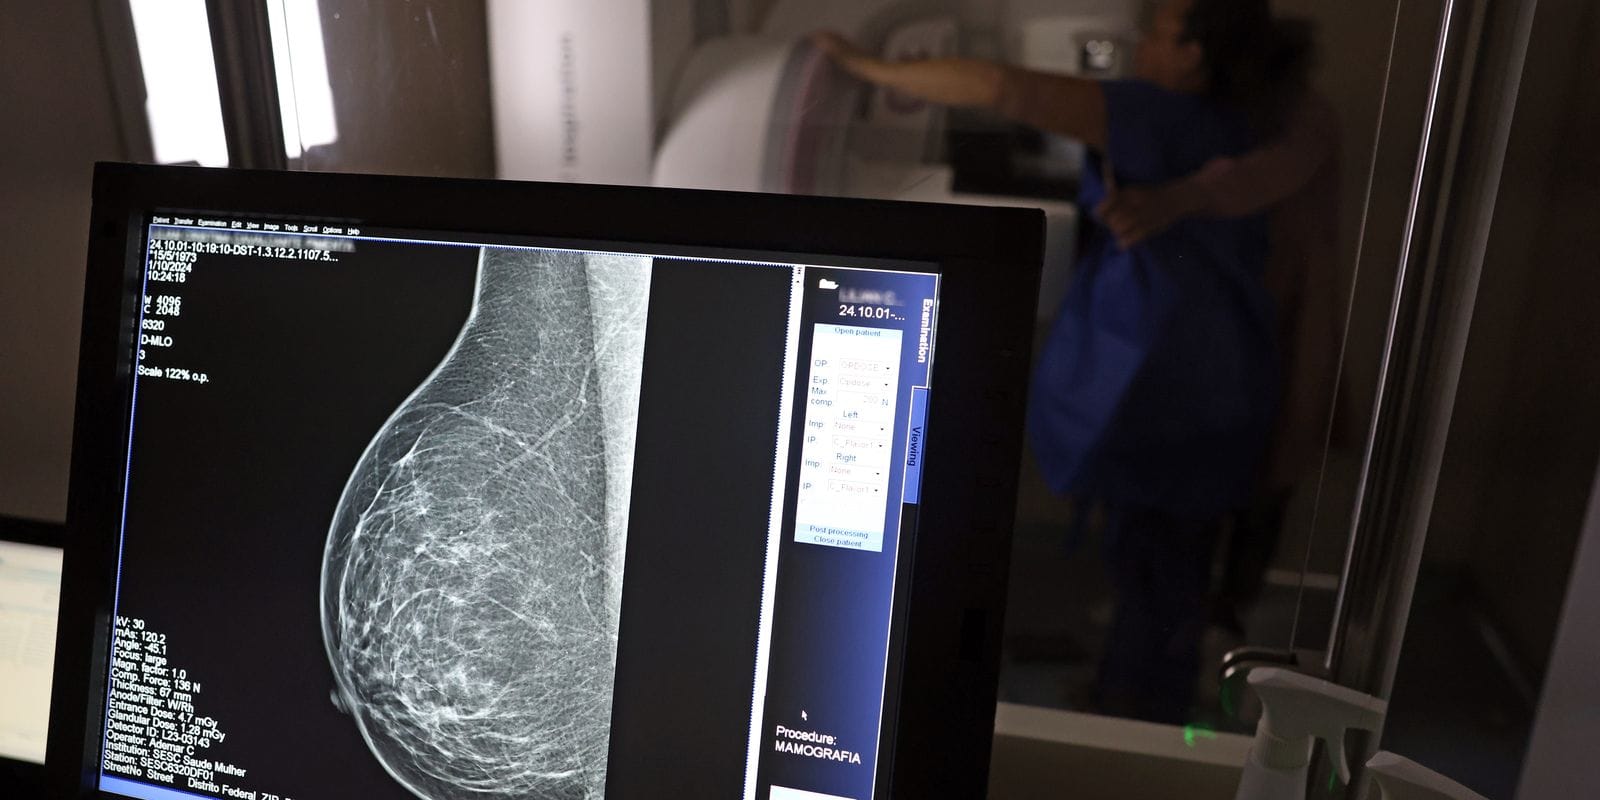

Embora o direito a essas folgas já estivesse presente na CLT desde 2018, a nova lei traz um avanço significativo: as empresas agora têm a obrigação de informar seus colaboradores sobre essa possibilidade. Além disso, a legislação inclui a divulgação de informações sobre campanhas de vacinação contra o HPV e o acesso a serviços para diagnóstico de cânceres de mama, próstata e colo do útero.

A Lei 15.377, sancionada pelo presidente Luiz Inácio Lula da Silva, não se limita apenas aos exames de câncer. Com a nova regra, os trabalhadores também poderão utilizar suas folgas para realizar exames preventivos relacionados ao HPV, ampliando assim o escopo de cuidados de saúde disponíveis para os funcionários.